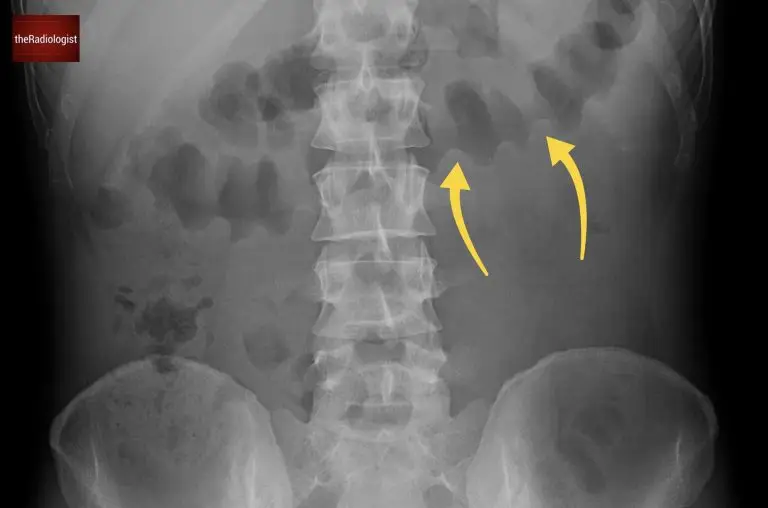

Where you see the bowel helps differentiate between small and large bowel. Dilated small bowel tends to be central, with valvulae conniventes traversing the full width of the bowel. Dilated large bowel lies more peripherally and shows haustra that do not cross the entire wall.

A case of large bowel obstruction. Here is the transverse colon and we can see indentations called haustrae that do not traverse the whole bowel wall.